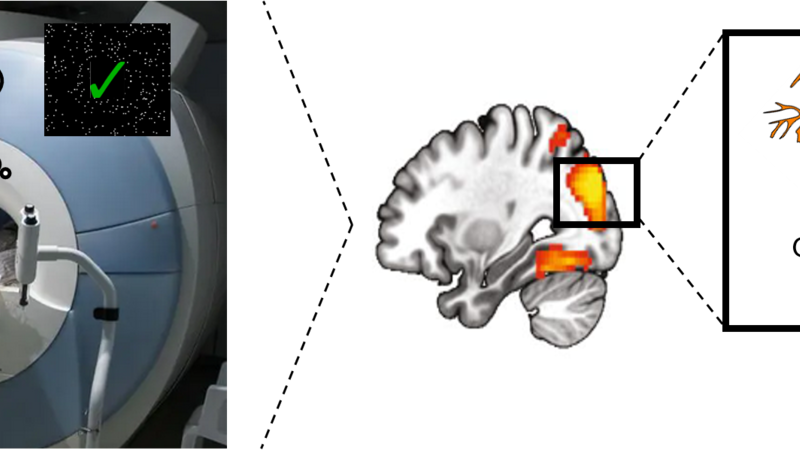

We utilise multi-modal brain imaging to study the complex interaction between neurochemical and structural brain plasticity that occurs during extended learning. Using magnetic resonance spectroscopy, we can determine how the release of inhibitory and excitatory neurotransmitters is calibrated during the learning of a new skill. Thanks to recent advances in mutli-parameter brain imaging, we are able to relate these neurochemical changes to alternations in brain structure, including levels of ‘myelin’, a molecule that wraps around microscopic segments of neurons to increase their firing speed. By combining these measures with functional imaging brain-wide network activity, we can elucidate how these neurochemical and neuroanatomical alternations impact brain activity during learning.